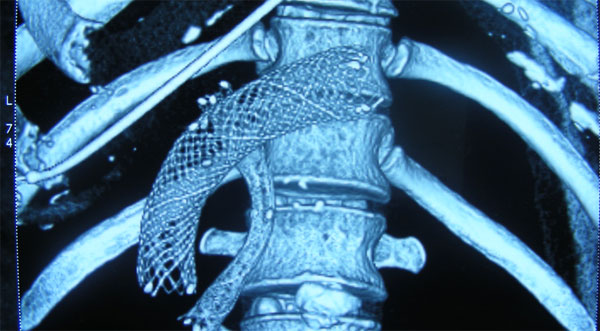

Endoscopic Placement of Self Expanding Metal Stents in Bile Duct and Outlet of Stomach